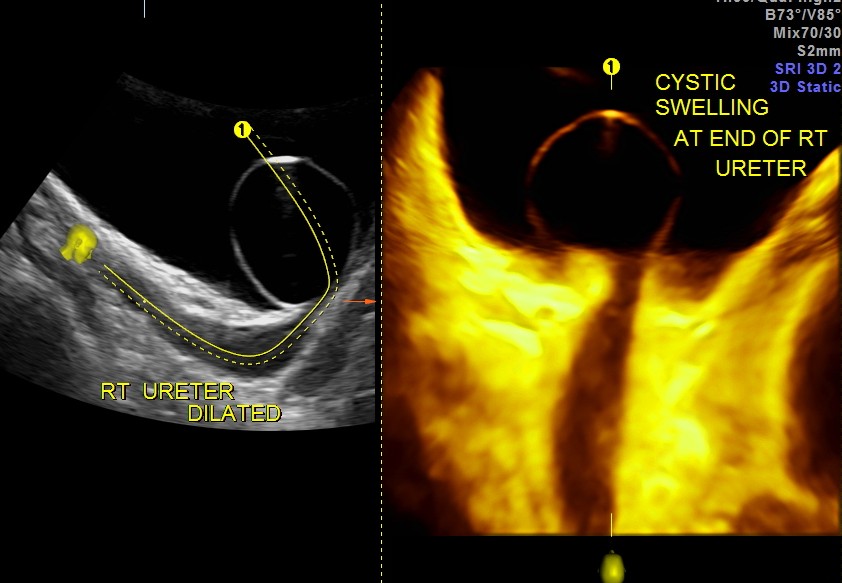

The urinary bladder showed the following :

given below are few other reconstructions

The patient was seen by the urologist and an IVP was done , which proved the diagnosis of orthotopic ureterocele . (a ureterocele entirely within the bladder.)